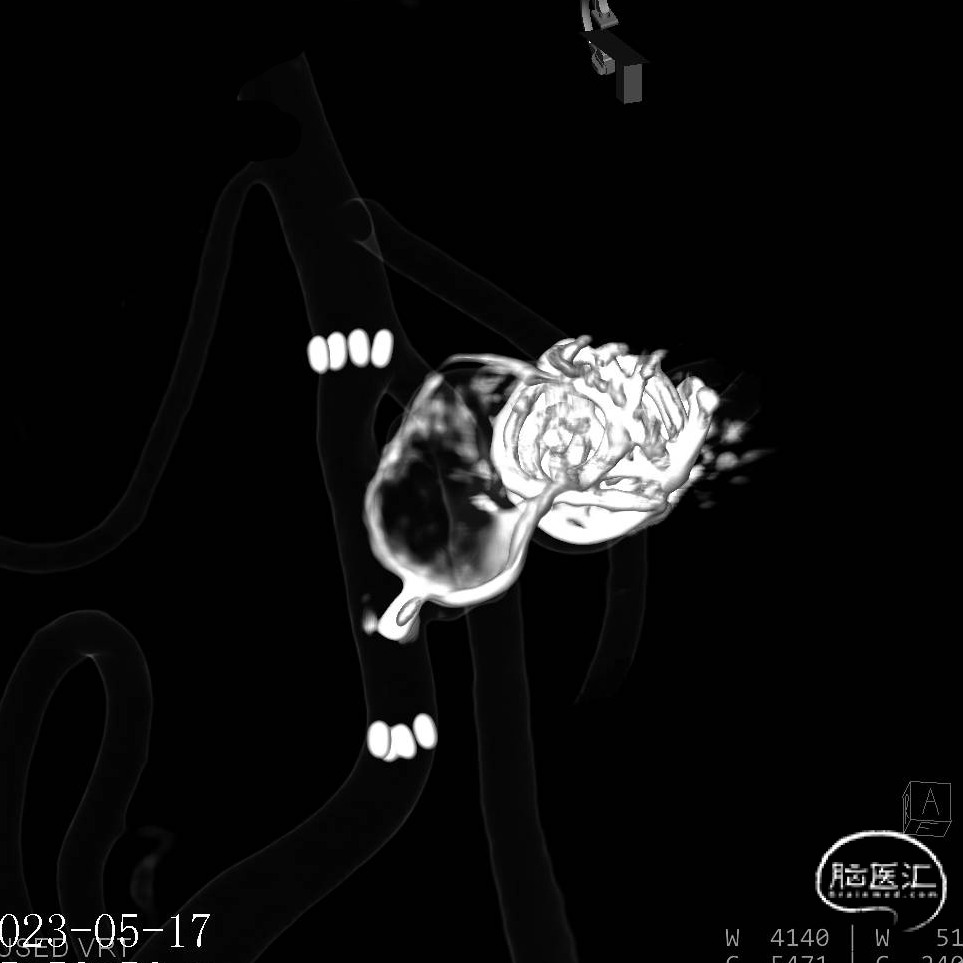

缓慢推出WEB™从种子至萌芽状态,继续向瘤腔内远端缓慢推送WEB™至萌芽至开花间状态;将WEB™和VIA™送至瘤顶,固定WEB™推送杆回撤VIA™,WEB™完全释放。

经造影可见WEB™尺寸合适,贴合瘤壁,小脑上动脉分支,大脑后动脉分支等血流通畅。解脱后,再次造影和Dyna-CT评估,可见动脉瘤瘤腔内有明显造影剂滞留,小脑上动脉瘤显影良好,分支血管血流正常。

基底动脉末端动脉瘤不显影,动脉瘤完全闭塞,WEB™完全栓塞。